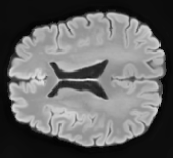

FLAIR

[Uncaptioned image] [Uncaptioned image] [Uncaptioned image]

T1

Ground Truth

Unimodal

Offline synthesis

Proposal

Table 2: Segmentation results for all proposed methods, each column represent a different slide in the image, blue areas are regions which were correctly labeled, false positives are shown in green, and false negatives in yellow

In order to better understand the above results, we visually analyzed the output segmentation performed for each method. Table 2 shows the results for three different slices (one slice per column). As illustrated, the proposed method is able to produce less false positives. It is also important to note that, unimodal segmentation is the one that produces more false positives, showing the advantage of using synthetic data. Regarding the nature of false positives, it can be easy to see in the third column a large number of false positives are on the border of periventricular lesions for the Unimodal method in comparison to the proposed method. Also from the first and second column, it can be observed that Unimodal tend to produce more small regions of false positives near to cortical areas. Removing such false positives requires additional post-processing steps, therefore, it is of value avoid this kind of over-segmentation. It can also be noted that synthesis methods tend to produce the same kind of false negatives, this may be due to the blurring effects in synthesized images since the information available during testing is limited – which otherwise is available from a FLAIR sequence.